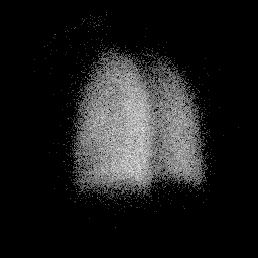

Posterior Perfusion Posterior Ventilation

norm_perf.gif (12668 bytes) norm_vent.gif (11969 bytes)